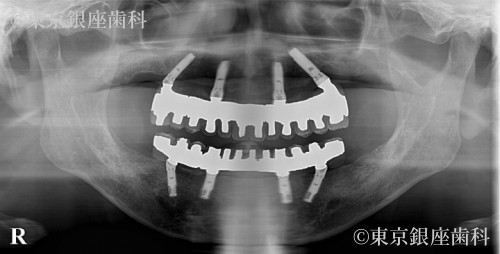

がん治療の既往があり複雑な治療歴を経てワンデイインプラントで噛む機能を回復した70歳代男性の症例

長年の治療で口腔内がつぎはぎ状態で違和感を抱えていたが、ワンデイインプラントで即日改善。1箇所結合不全があったが再手術で問題なく回復した。

ワンデイインプラント(上下)